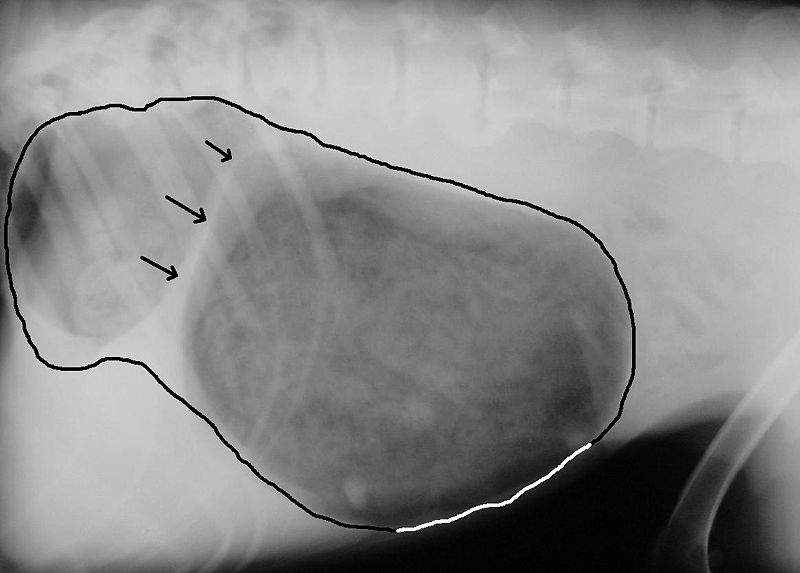

Der Magen ist nur an zwei Stellen“aufgehängt“, am 12-Fingerdarm und auf der anderen Seite an der Speiseröhre. Er pendelt also immer etwas.

Dreht sich der Magen, werden Blutgefäße abgedrückt, das Herz wird stark belastet und der Bauch bläht auf.